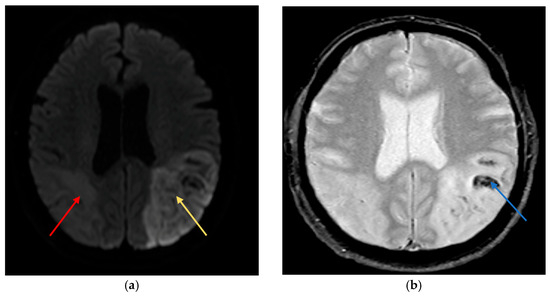

Non-contrast computed tomography (CT) of the head demonstrated an evolving acute infarct in the right posterior parieto-occipital region with poorly defined hypodensity, white matter oedema, and mild mass effect (Figure 1). Apixaban was immediately withheld, and aspirin was commenced after coagulation screening. MRI brain was requested to rule out a space-occupying lesion.

Figure 1. Non-contrast axial Computed Tomography (CT) of the brain showing an evolving infarct in the right posterior parietal lobe (white arrow), characterised by ill-defined hypodensity and loss of grey-white matter differentiation, consistent with acute ischaemic stroke. There is no significant midline shift or haemorrhage noted.